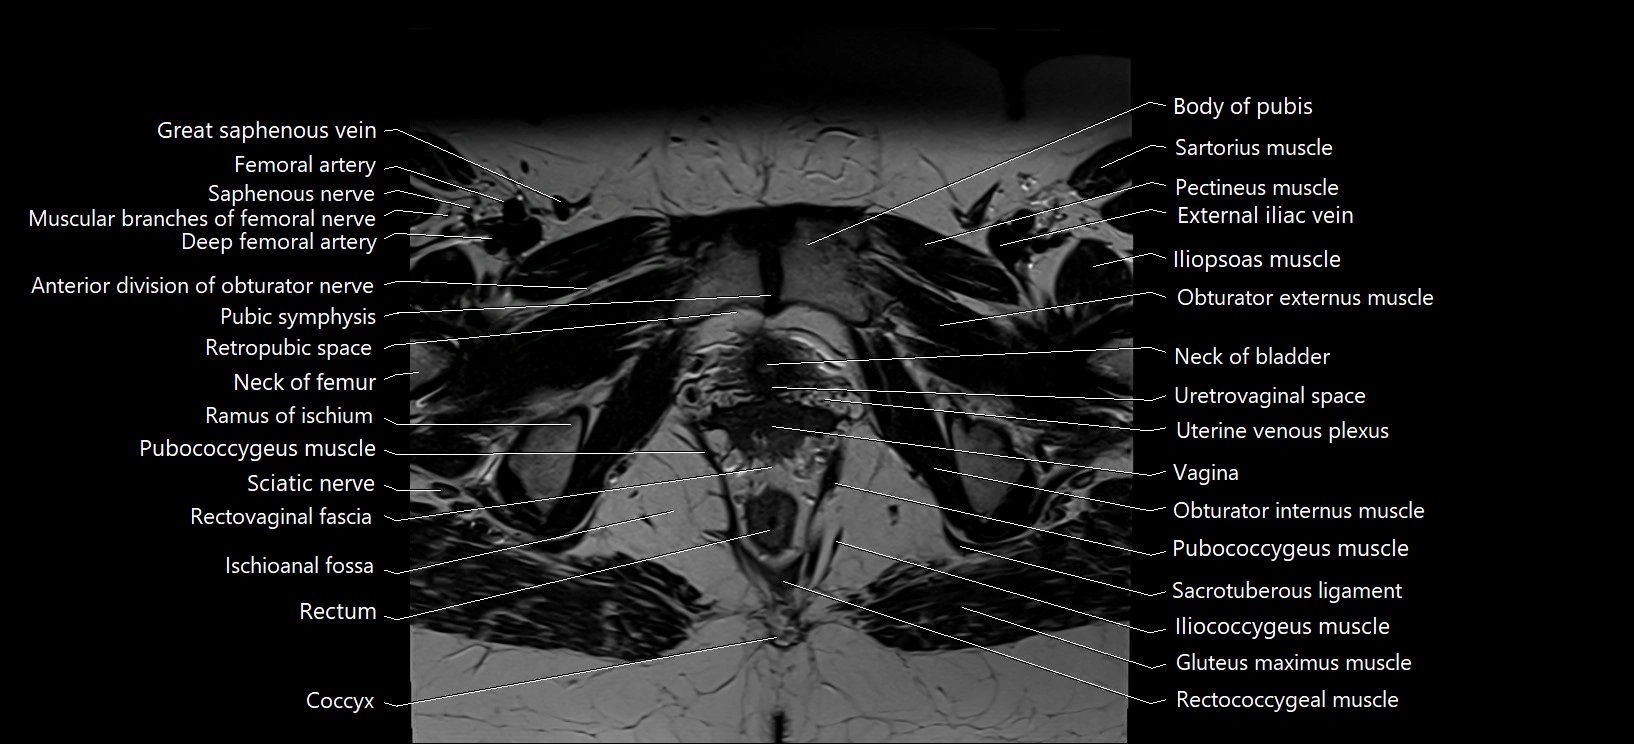

- Body of pubis

- Coccyx

- Iliococcygeus muscle

- Ischioanal fossa

- Median umbilical ligament

- Neck of urinary bladder

- Obturator externus muscle

- Obturator internus muscle

- Pubic symphysis

- Pubococcygeus muscle

- Ramus of ischium

- Rectococcygeal muscle

- Rectum

- Retropubic space

- Sacrotuberous ligament

- Saphenous nerve

- Sartorius muscle

- Sciatic nerve

- Urethrovaginal space

- Uterine venous plexus

- Vagina